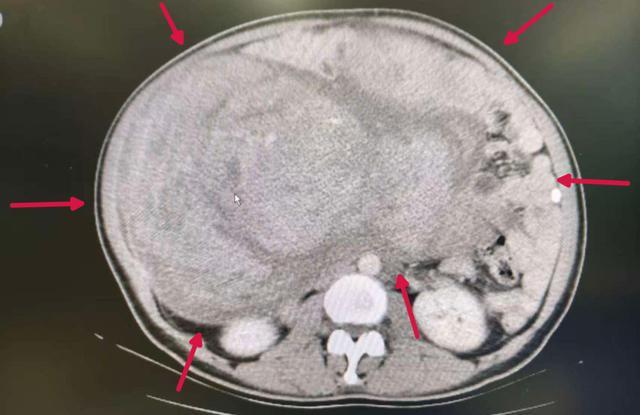

(▲患者腹部CT)

CT检查显示,她的子宫已增大至足月妊娠大小,且腹腔内存在突破超声探测范围的巨大包块,该肿物与子宫分界模糊,内部呈现复杂回声特征,已对膀胱、直肠等重要脏器形成严重压迫。